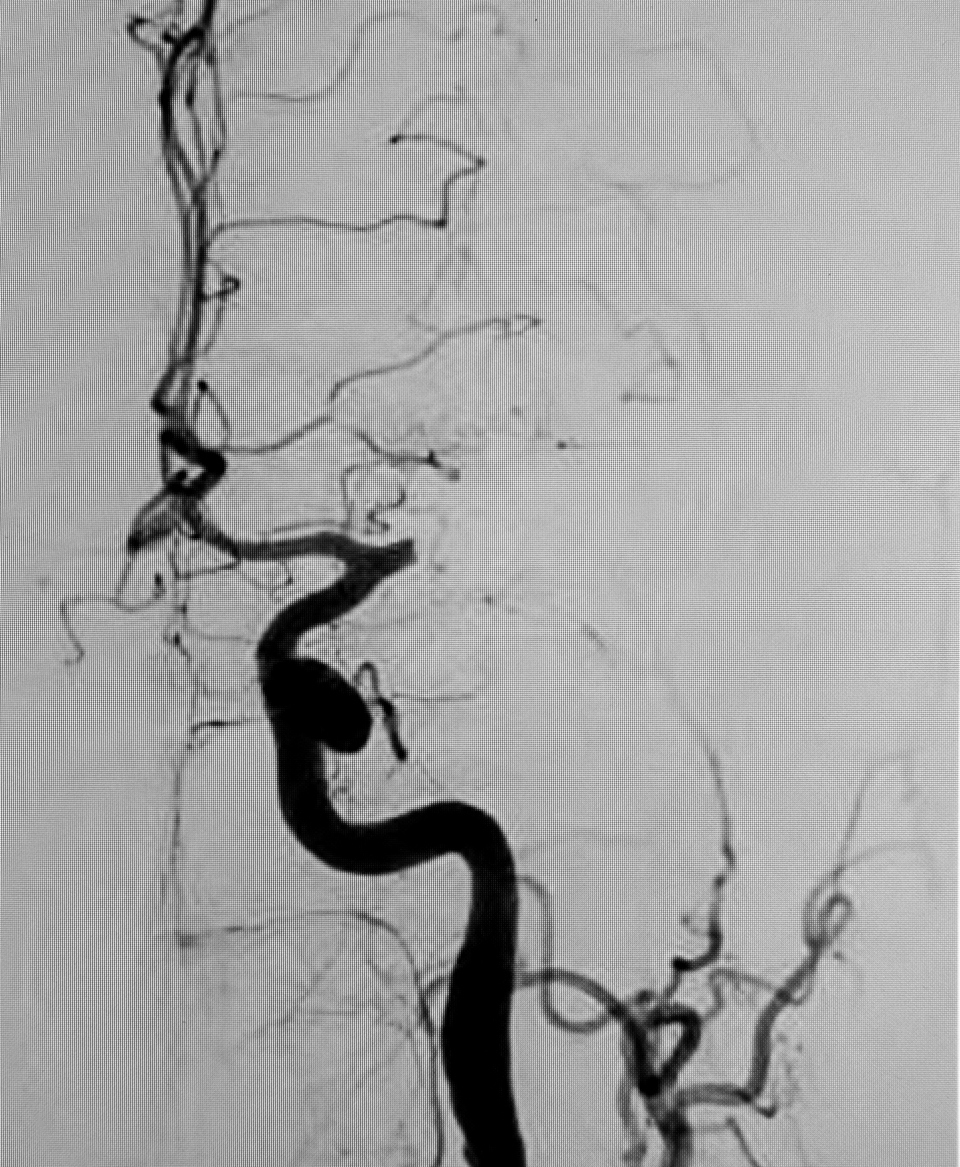

Hvis ikke, er det en rigtig god idé at øve den, så den sidder på rygraden. Remsen er enkel og god at huske, fordi den handler om de tre hyppigste og let genkendelige symptomer på stroke, som er en samlet betegnelse for en blodprop eller blødning i hjernen.